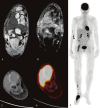

Case report: A 62-year-old woman with FIGO stage IIIB endometrioid adenocarcinoma, previously treated with surgery and radiotherapy, presented with progressive pain and swelling of the right foot. Initial clinical evaluation suggested cellulitis, and empiric antibiotics were started. Symptoms persisted, prompting further investigation. MRI demonstrated diffuse marrow abnormalities and cortical disruption in multiple tarsal bones, raising suspicion for malignancy. Biopsy confirmed metastatic endometrioid adenocarcinoma. FDG PET-CT revealed intense uptake in the foot lesion, as well as additional FDG-avid lesions in the right femur, fibula, metatarsal, and a pulmonary nodule, consistent with widespread metastatic disease.